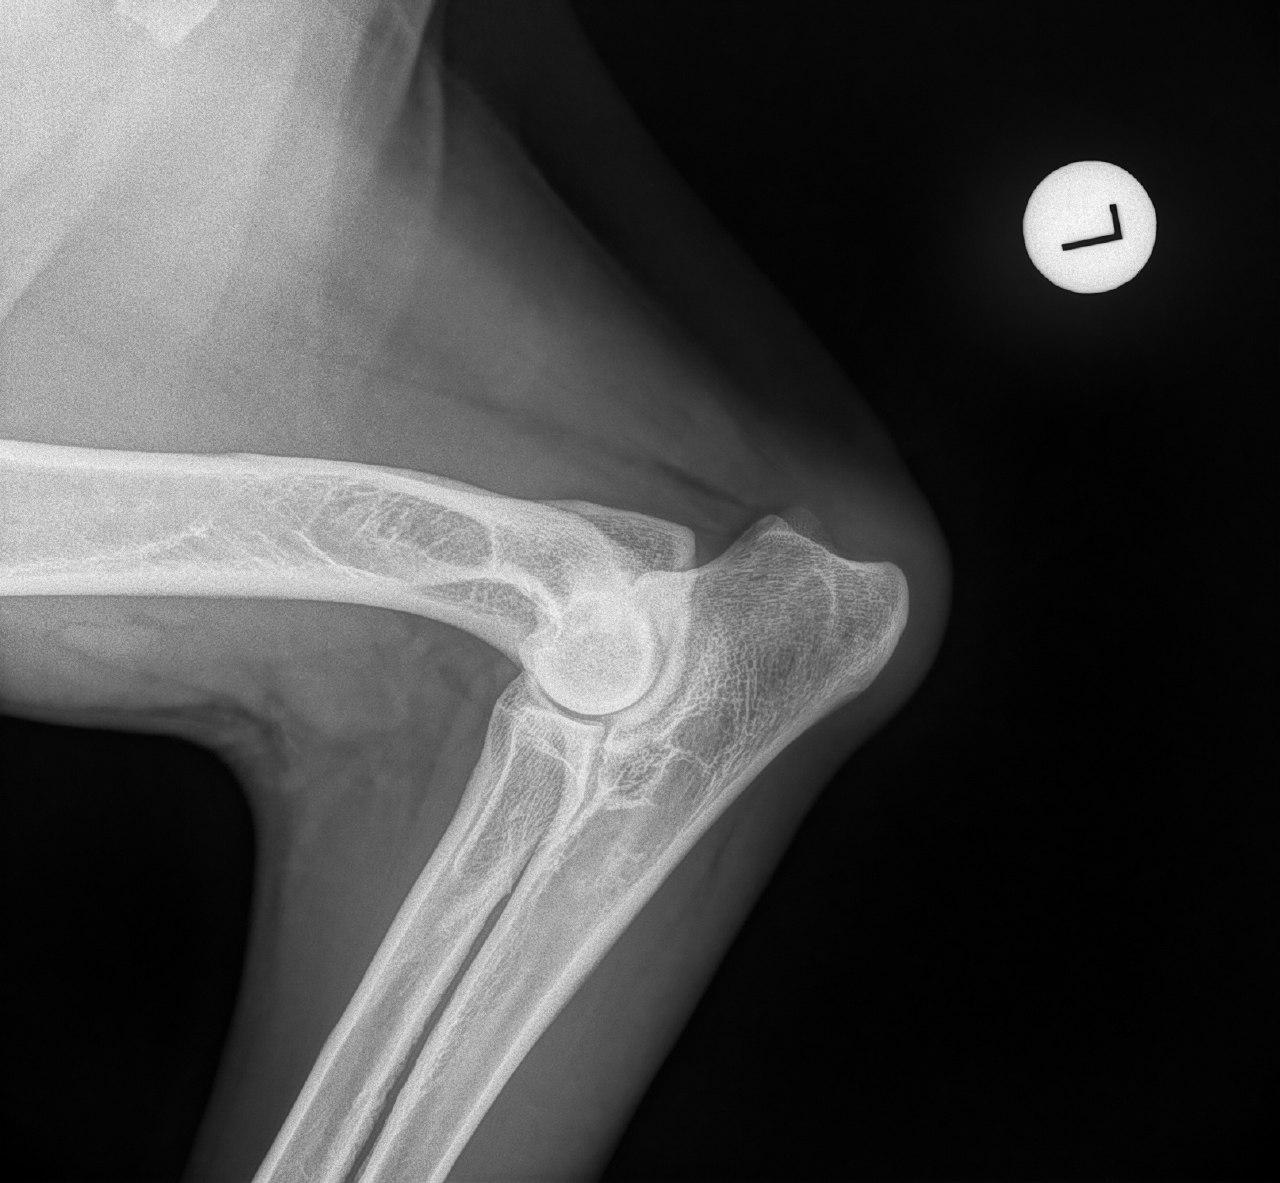

Mit der HD ist das so ne Sache..... die Vererbung spielt eine sehr große Rolle, ja. Aber bei unserer Peggy Zb ist es so, dass mehrere Generationen nachweislich HD und ED frei sind und auch frei von Spondylosen. Als einziger Hund überhaupt in der gesamten Zucht hat unsere Dame alles mitgenommen, was zu kriegen war;(: sie hat nicht nur schwere HD, weil ihre Hüfte viel zu locker ist, sondern dadurch bedingt am rechten Knie bereits schwere Arthrose und hinten links eine Sehenschwäche (durch Überlastung), weshalb sie dort durchtrittig ist. Und als würde das alles nicht schon vollkommen reichen, wurden aktuell auch noch mehrere heftige Spondylosen diagnostiziert;(. An einer Stelle ist sogar schon etwas abgebrochen8|.